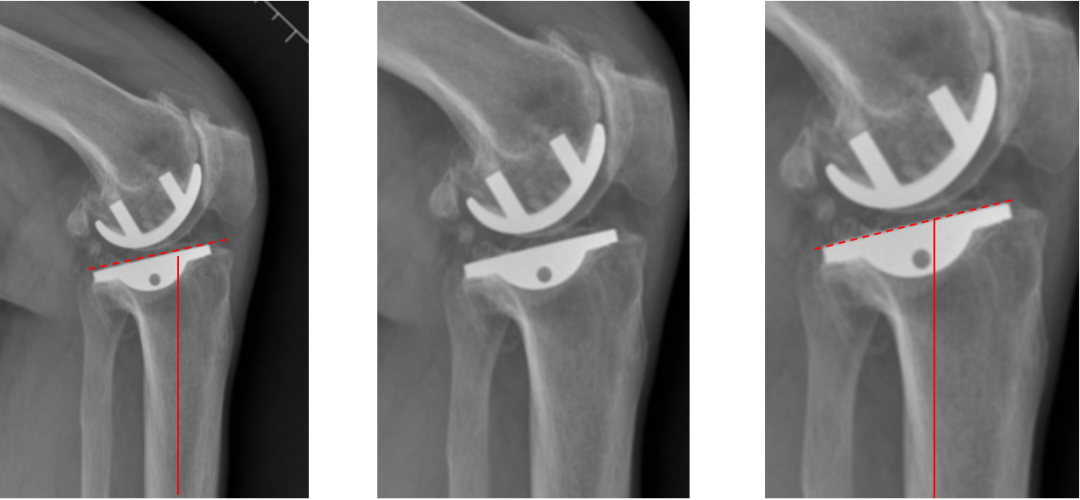

侧位片标准胫骨和股骨假体位置

侧位片假体位置:股骨假体长栓与短栓平行,后倾35°;假体后缘与股骨后髁齐平,胫骨假体后倾7°,与胫骨平台前后缘齐平。

胫骨假体偏大,且后倾不足

侧位胫骨假体位置:胫骨假体后侧悬挂>2mm,后倾2°。

胫骨假体后倾角度大

侧位片胫骨假体位置:胫骨假体后倾12°,前后缘齐平 。

股骨假体偏小

侧位片股骨假体位置:股骨假体偏小,与胫骨假体后缘不齐平;屈曲15°,未包容股骨后髁。

股骨假体偏大

侧位片股骨假体位置:股骨假体与胫骨假体不匹配,股骨假体大一个型号,屈曲45°,后缘空虚。

股骨假体屈曲角度大

侧位片股骨假体位置:股骨假体与胫骨假体匹配,股骨假体屈曲62°,前缘翘起。